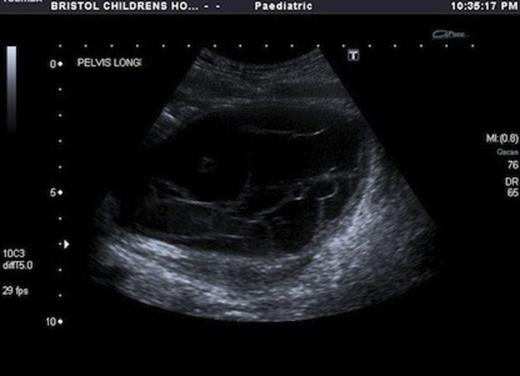

USS showed a septated cystic structure behind the bladder and abutting the ovary. There was echogenic fluid within the cysts. (Fig 1&2)